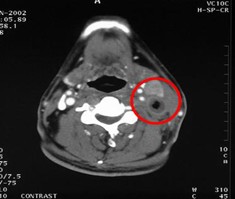

患者病情:鼻咽癌,左頸前、后兩個淋巴結(jié)轉(zhuǎn)移,大小近似,均為5.7cm2。治療方案:前淋巴結(jié)接受放療40Gy,后淋巴結(jié)注射今又生1×1012VP/次/周×4,聯(lián)合40Gy放療。治療后,前、后淋巴結(jié)體積均縮小,前淋巴結(jié)縮小到2.9cm2,縮小40%;后淋巴結(jié)縮小到1 cm2,縮小72%,而且CT可見其內(nèi)部空洞壞死,無癌細胞。

治療前

治療后